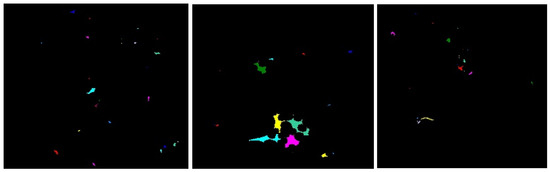

2.3.1. Connected Components

2.3.2. Watershed Segmentation